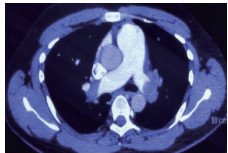

1 经典的挽救性溶栓治疗策略可能带给医生更多的是被动和难度例1 男性,28岁,体质量90 kg。主诉“胸闷、憋气1周加重1 d”。既往:体健;喜久坐(平均10~15 h/d);否认手术史、外伤史;入院查体:神志清楚,体温36.8℃,血压128/80 mmHg(1 mmHg=0.133 kPa),脉搏120次/min,呼吸26次/min,脉氧饱和度96%(安静,空气氧),未见明显乏氧征。双肺呼吸音清,未闻及干湿性啰音。心率120次/min,心律齐,P2 > A2,心界无扩大,无杂音。腹软,无压痛,肠鸣音正常,双下肢无浮肿。神经系统查体未见异常。血气分析(空气氧)提示pH 7.514,PaCO2 27.2 mmHg,PaO2 67.1 mmHg,SaO2 95.0%;D-Dimer:3 035 ng/mL,FDP 33.08 μg/mL,FBG 4.520 g/L;PLT 179.0 G/L,TNI 0.08 ng/mL,BNP 882.00 pg/mL;ALT 38 U/L,AST 17 U/L,CREA 82.6 μmol/L,血Na+、K+、Cl-正常范围;超声心动图(Ultrasonic Cardiogram,UCG)提示:右心增大,肺动脉主干及右肺动脉增宽,肺动脉主干32 mm,三尖瓣反流(重度),反流面积8.6 cm2,TI法估计SPAP为67 mmHg、左室舒末内径50 mm、左室E/A:45/38 cm/s, 左室壁厚度及运动正常,未见节段性室壁运动障碍;双下肢静脉超声提示左侧股静脉血栓形成可能(完全型)。心电图(图 1所示)提示窦性心动过速;肺动脉增强CT(Computed tomographic pulmonary angiography, CTPA)提示双肺主干明确充盈缺损(图 2所示)。入院诊断:急性肺血栓栓塞症(中高危)。入院后给予抗凝治疗(依诺肝素钠90 mg,皮下注射,1次/12 h)重叠华法令治疗的第4天D-Dimer升至47 482 ng/mL,第6天2 411 ng/mL。第7天常规复查双下肢超声未见新增血栓形成,复查UCG(当天INR 2.25)提示右心房漂浮血栓,并随心脏蠕动明显(图 3所示)。在准备胸外科手术取栓的过程中出现血压下降至70/40 mmHg,脉氧饱和度降至45%,立即给予气管插管并系统溶栓治疗(r-tPA 100 mg于2 h输注),溶栓治疗1.5 h患者血压逐渐回升并趋于稳定、溶栓治疗3 h自主呼吸开始恢复,于插管3天后(住院第10天)拔出气管插管,成功撤离呼吸机。溶栓过程中曾经出现消化道、气道出血,血红蛋白下降1.9 g/dL,未予输血治疗。溶栓后复查CTPA提示双肺主干血栓负荷明显减少,远段血液灌注明显增加(图 4所示)。

| 图 2 入院时CTPA提示双肺主干明确充盈缺损 |